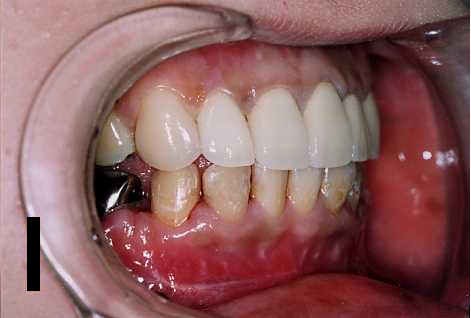

咬んだ際に、上の前歯より下の前歯が突出している状態を反対咬合といいます。

一般的に受け口と言われるものの中には、反対咬合・シャクレ顔があります。

下アゴの歯並びが上アゴよりも出ている場合を「受け口」、 専門用語では「下顎前突」と言います。下アゴが大きすぎたり上アゴが小さすぎたりするために生じ、コンプレックスに直結します。

反対咬合の最も簡便な代表的治療法として“受け口セットバック手術”が挙げられます。 この手術は、奥歯のかみ合わせ状態(前後方向)を触らないで、前方部(見えるところ)左右の4番までの歯だけを 部分的に手術する方法です。方法は4番の歯を抜歯して、3,5番の歯の間に隙間をつくります。

残った前歯の6本をひとかたまりに後退させる治療法です。